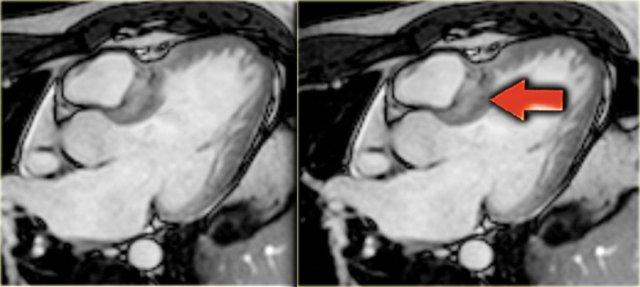

HCM với đường ra thất trái hẹp (mũi tên vàng), chuyển động ra trước tâm thu của lá van trước van hai lá (mũi tên xanh dương) và hở van hai lá (mũi tên đỏ)

Trên hình ảnh cuối tâm thu, có thể thấy các dấu hiệu sau (hình):

- Dòng phụt trong đường ra thất trái bị hẹp

- Chuyển động ra trước tâm thu của lá van trước van hai lá

- Hở van hai lá